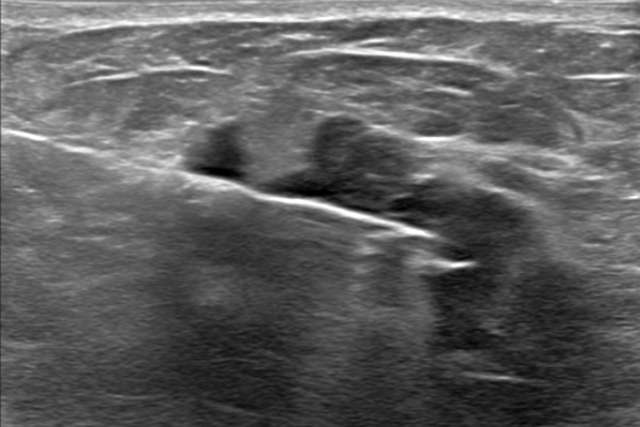

How to Work up

a Patient with...

Evaluating patients presenting with lumps, pain, nipple discharge, and more.

Delve into cases developed by our section to uncover key clinical presentations and image findings that can help guide your practice.